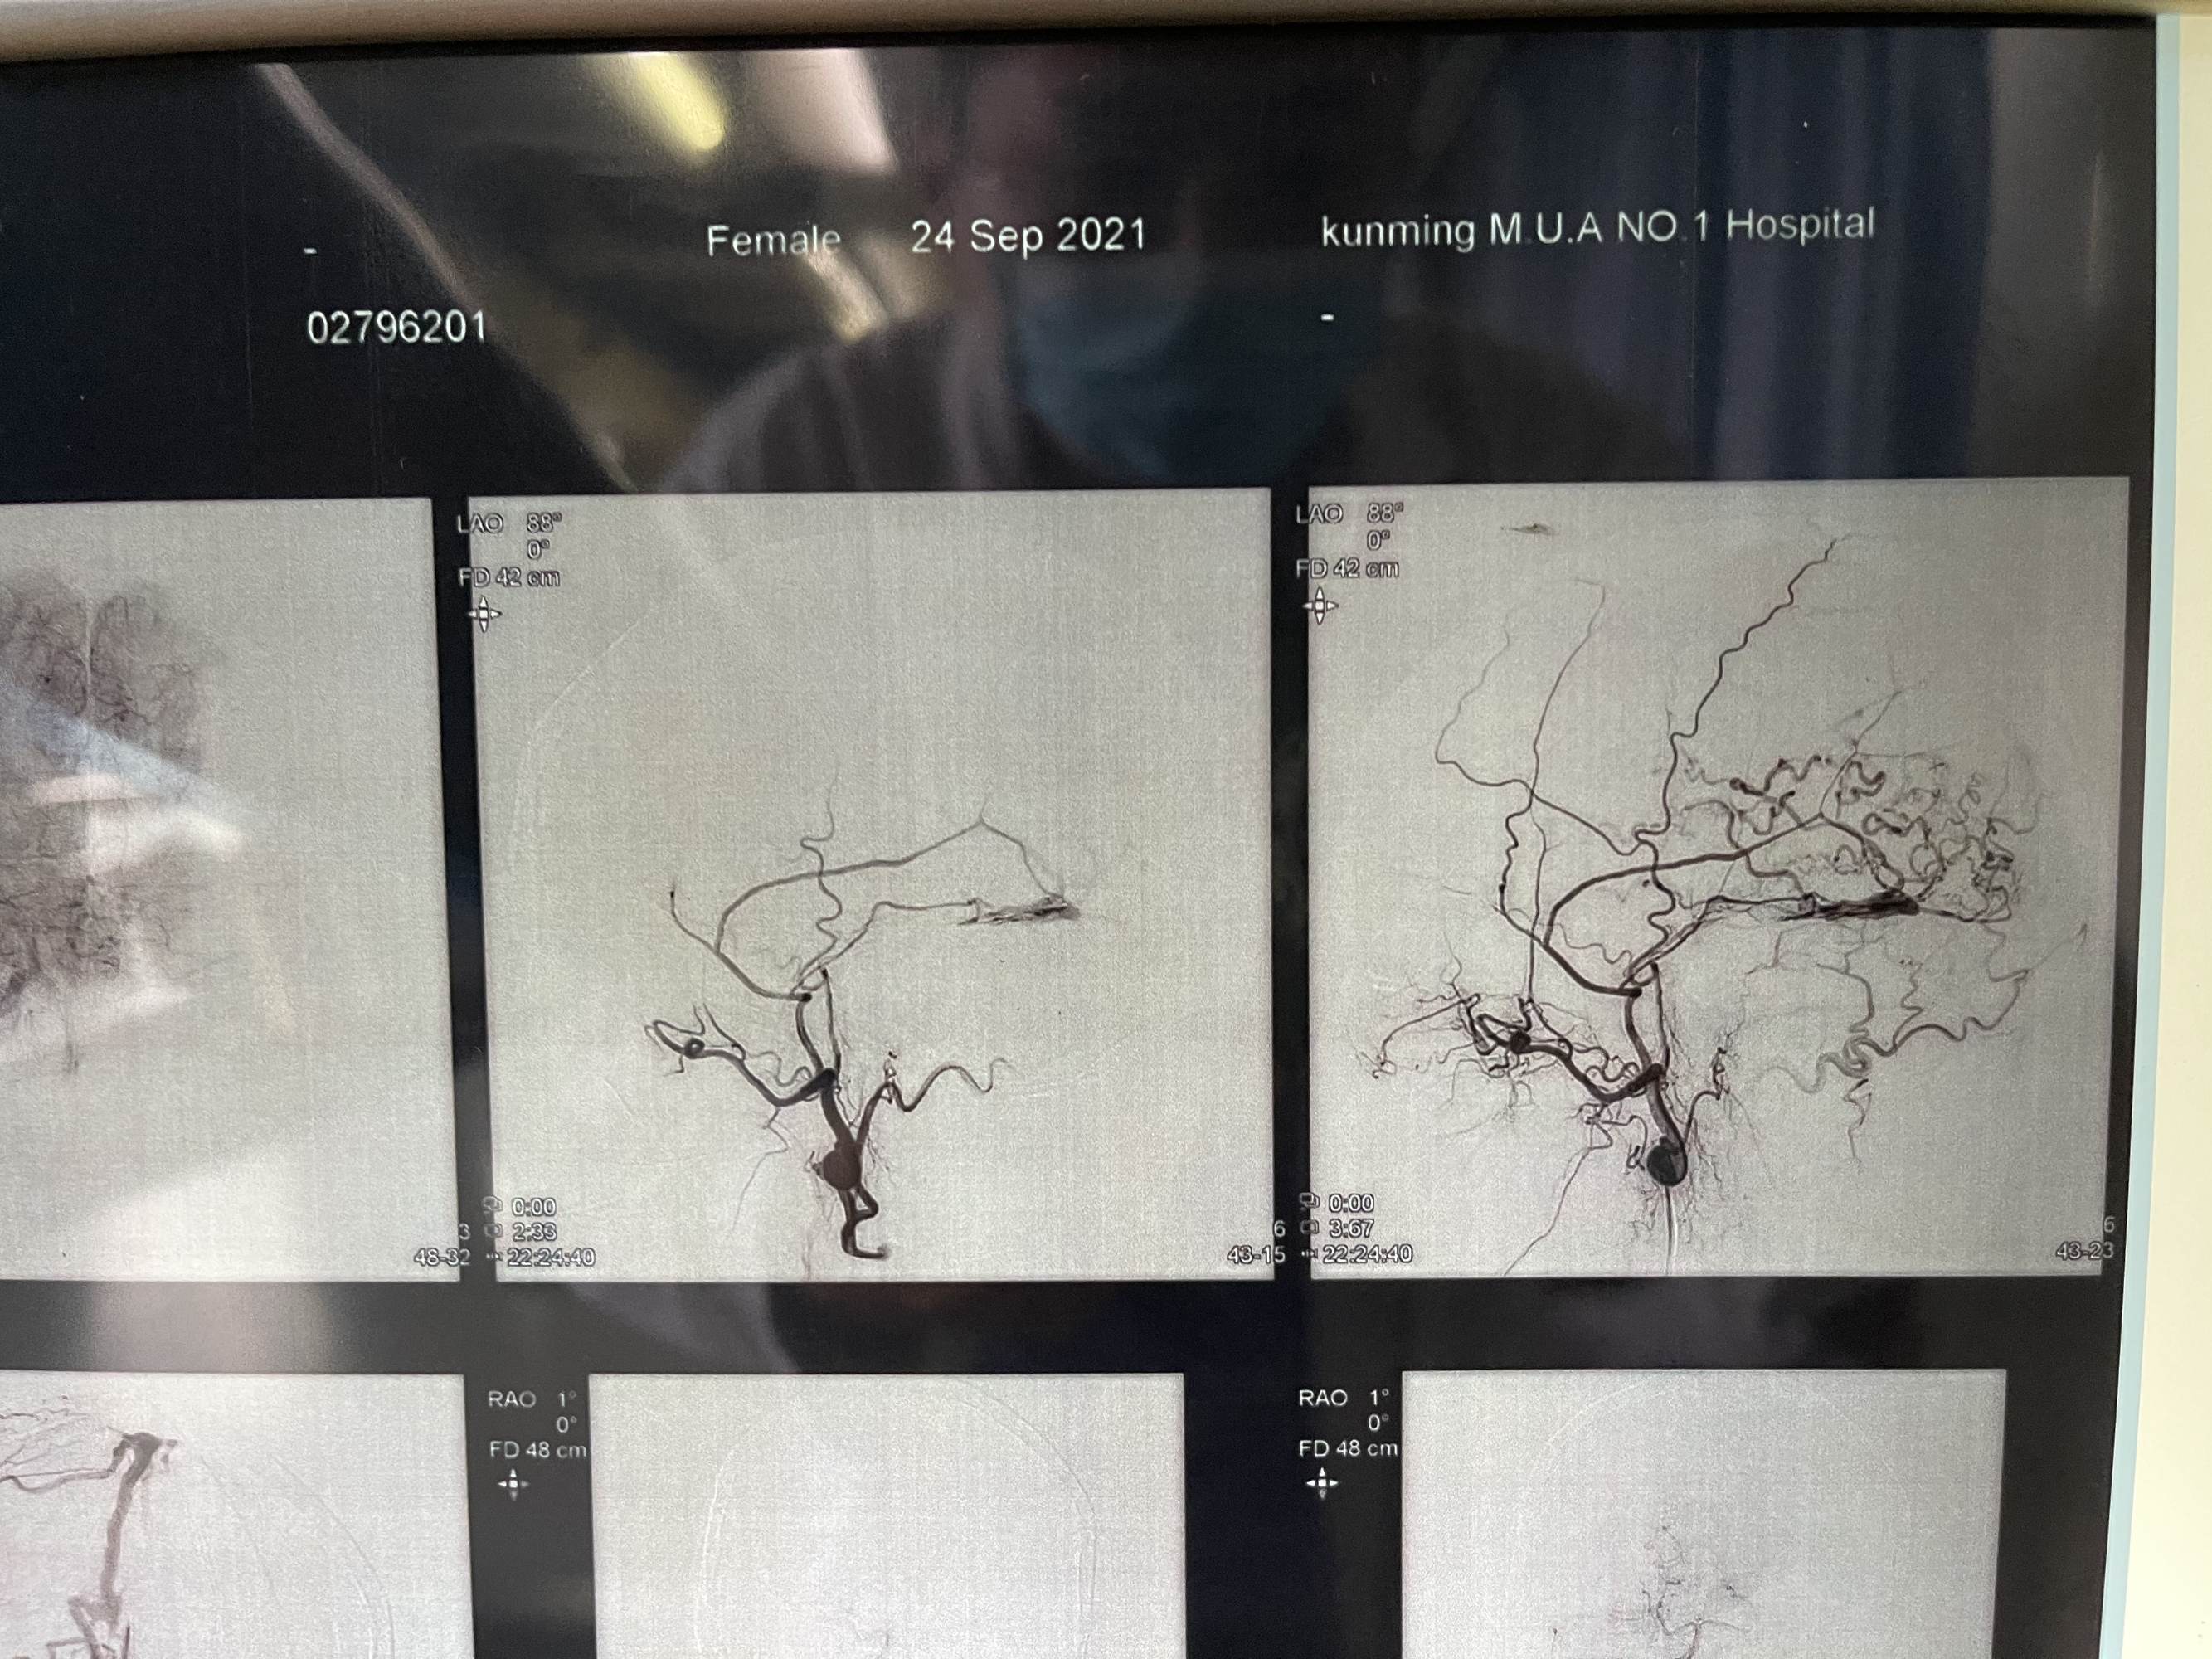

患者女性,68岁,头痛入院,行造影检查硬脑膜动静脉瘘,双侧脑膜中及枕动脉主要供血,开口位于枕部,皮层引流静脉代偿性粗大,拟介入栓塞

看看术前造影,迂曲的静脉,上矢状窦后三分之一及横窦已经不显影了

患者女性,68岁,头痛入院,行造影检查硬脑膜动静脉瘘,双侧脑膜中及枕动脉主要供血,开口位于枕部,皮层引流静脉代偿性粗大,拟介入栓塞

看看术前造影,迂曲的静脉,上矢状窦后三分之一及横窦已经不显影了